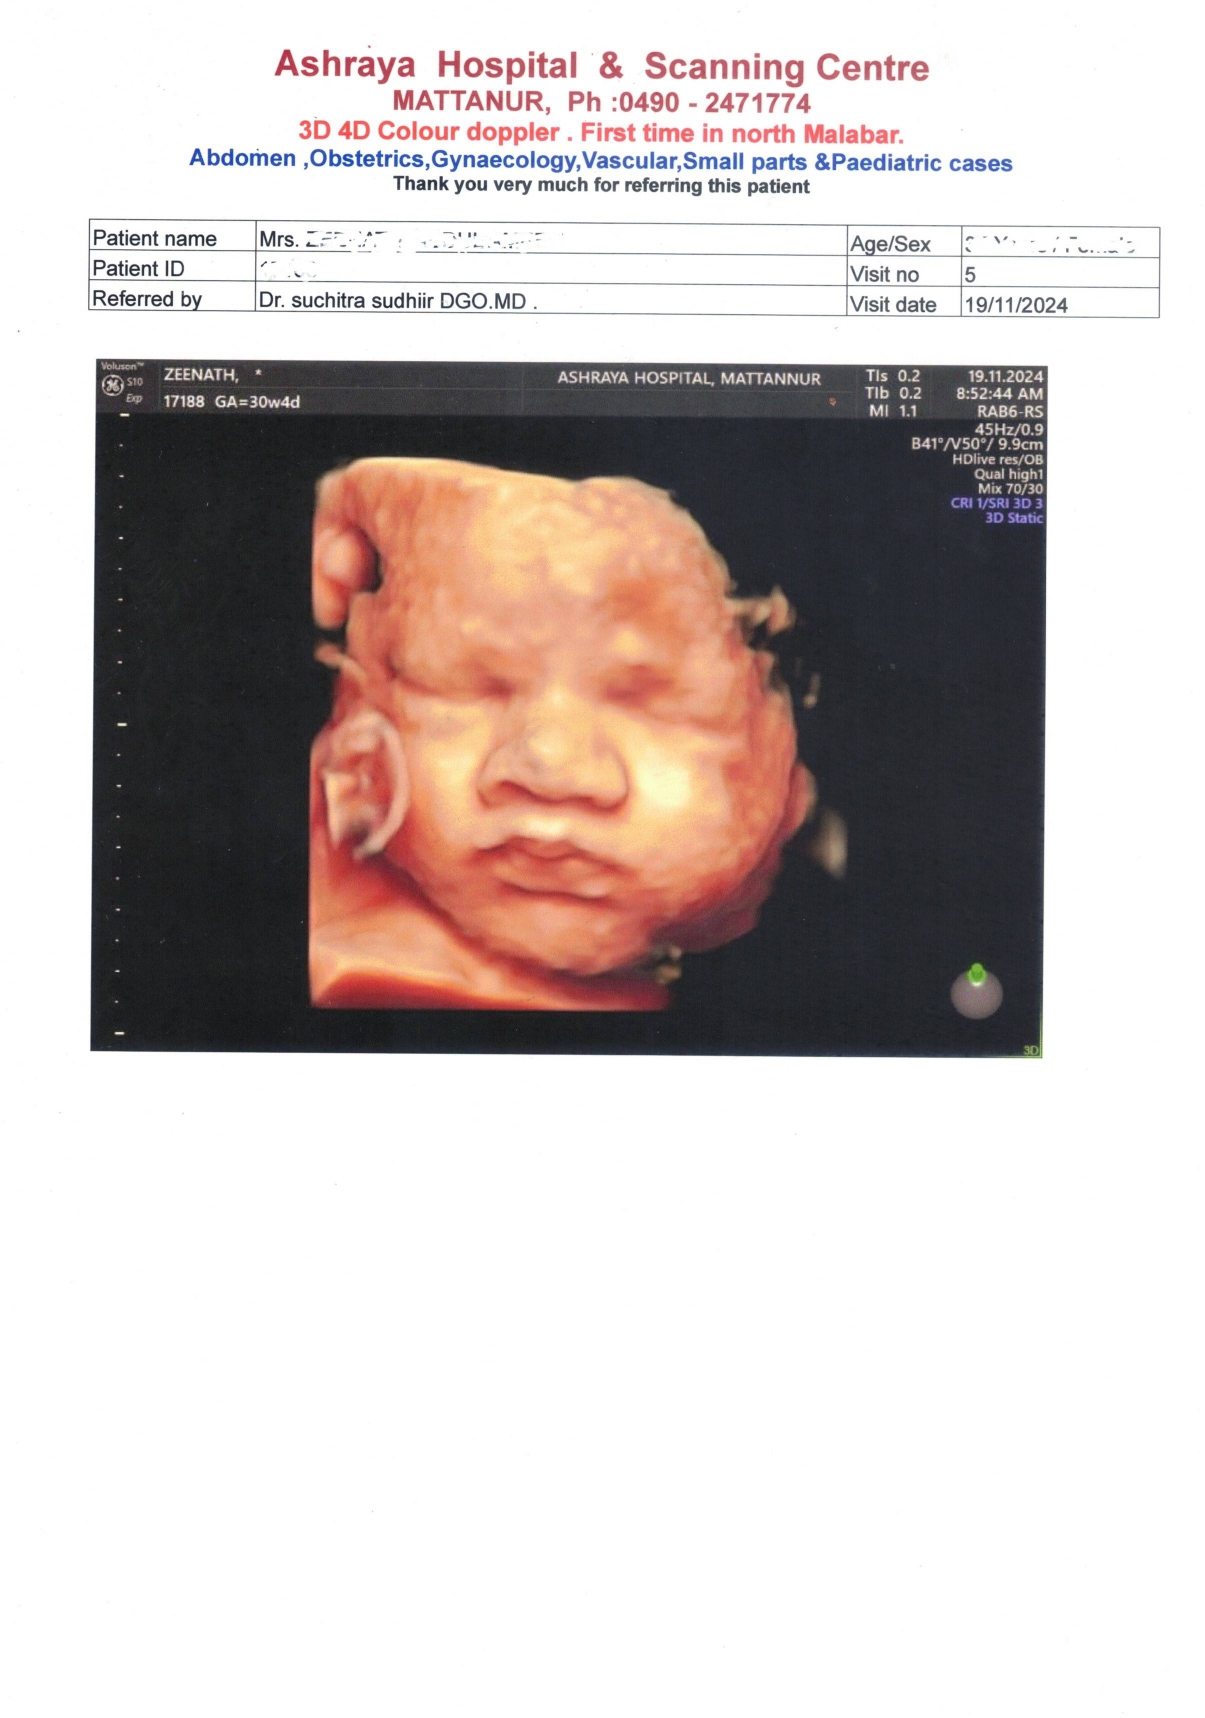

SCANNING REORT OF 30 WEEKS FETAL DONE AT ASHRAYA